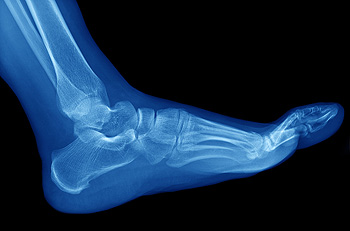

What Is a Navicular Stress Fracture?

One of the foot's 26 bones is called the navicular bone, which sits just in front of the ankle on…